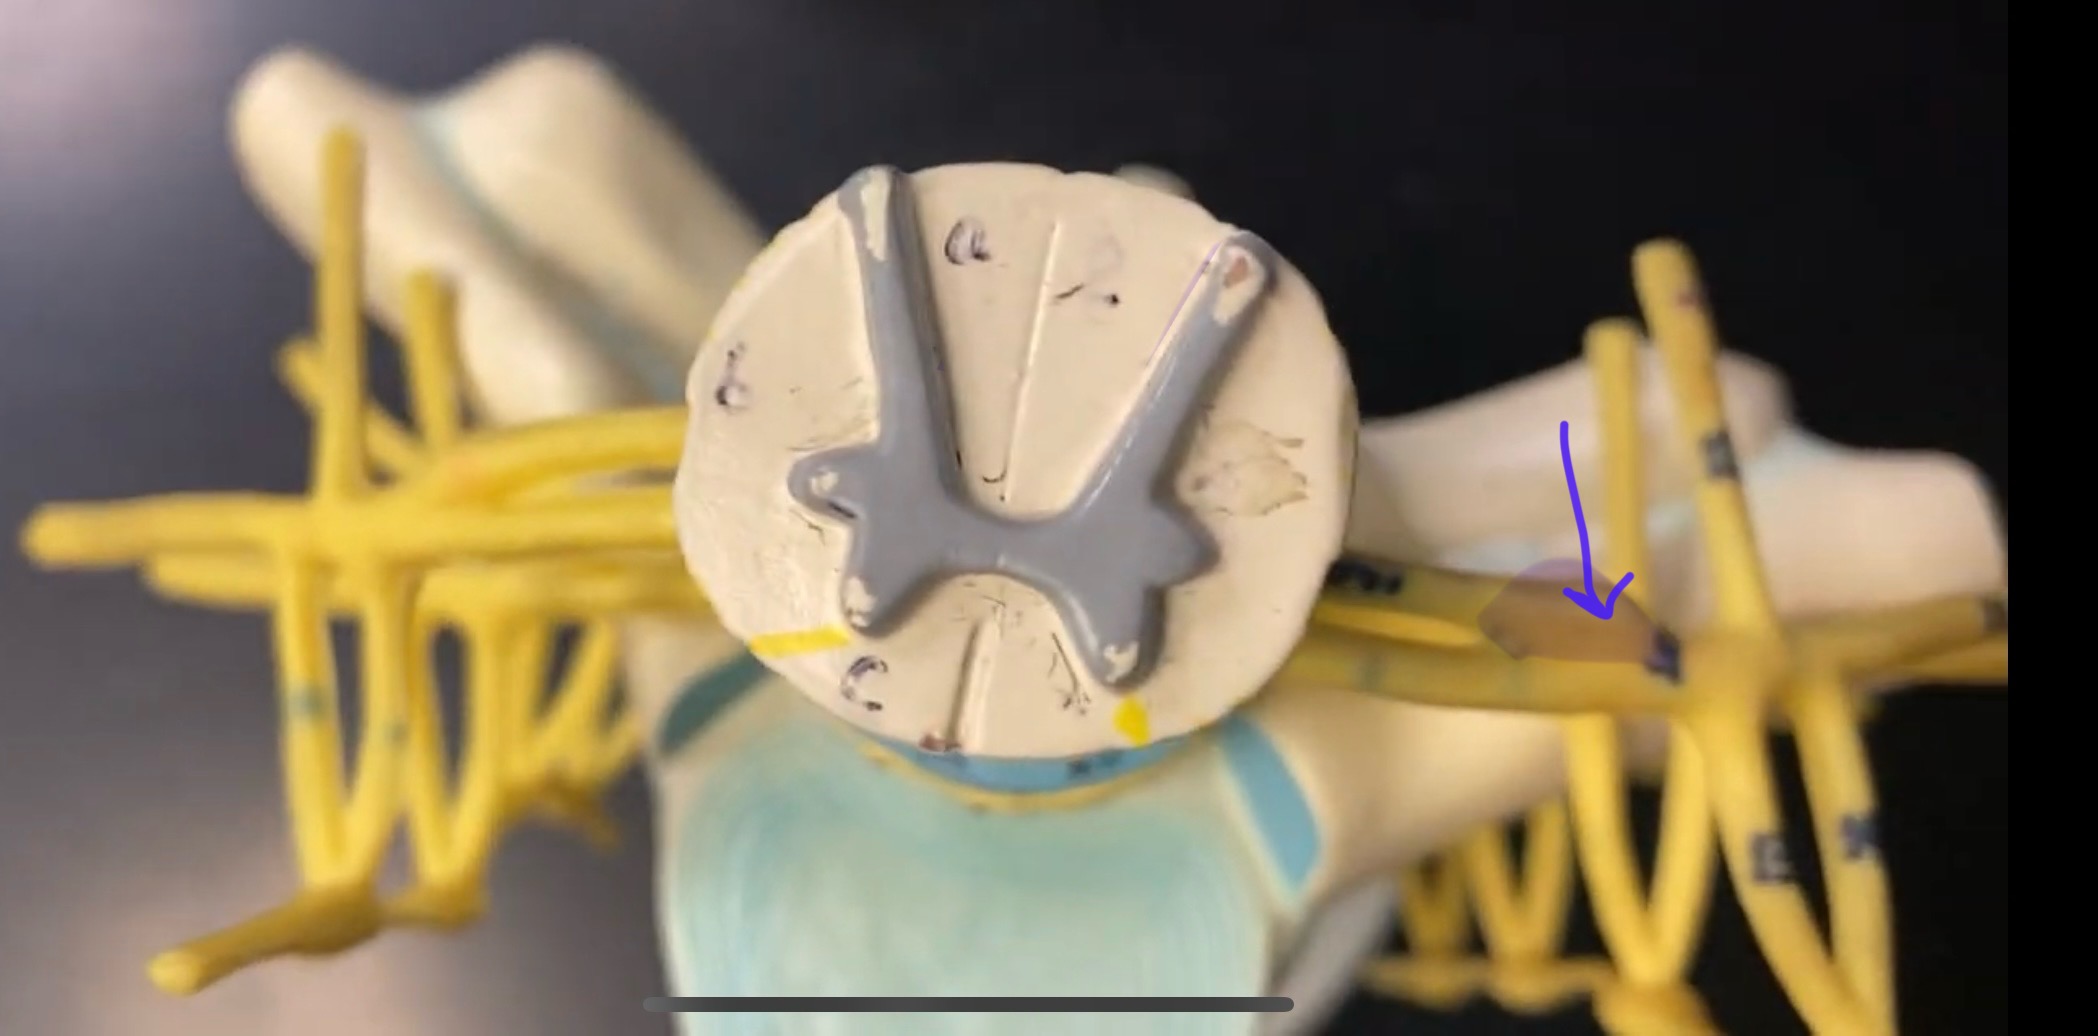

What type of spinal nerve is this? How many pairs?

cervical (8 pairs)

What type of spinal nerve is this? How many pairs?

thoracic (12 pairs)

What type of spinal nerve is this? How many pairs?

lumbar (5 pairs)

What type of spinal nerve is this? How many pairs?

sacral (5 pairs)

What type of spinal nerve is this? How many pairs? (not pictured)

coccygeal (1 pair)

rami communicantes

rami communicantes

sympathetic chain ganglia

sympathetic chain ganglia

cervical plexus – phrenic nerve

cervical plexus – phrenic nerve

brachial plexus – ulnar nerve

brachial plexus – median nerve

brachial plexus – radial nerve

lumbar plexus – femoral nerve

lumbar plexus - femoral nerve

sacral plexus – sciatic nerve

sacral plexus – sciatic nerve